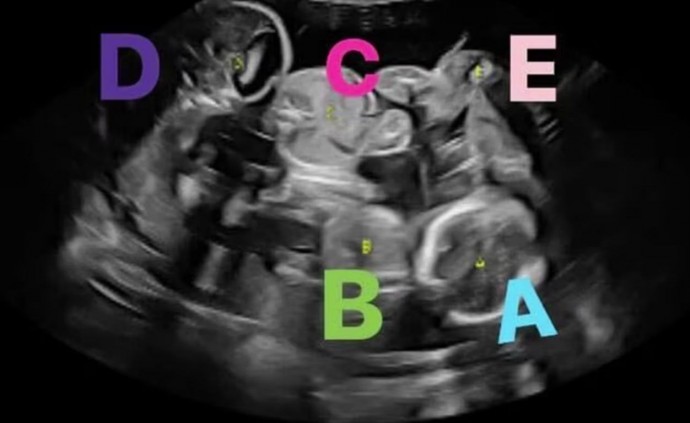

26-летняя Эшли Мейерс не планировала больше рожать и была удивлена, когда поняла, что беременна. Анализ крови показал, что у неё будет двойня. Когда пара пришла на УЗИ, супруги ожидали увидеть двух эмбрионов. Однако врач сказал, что Эшли беременна пятью детьми: двумя мальчиками и тремя девочками.